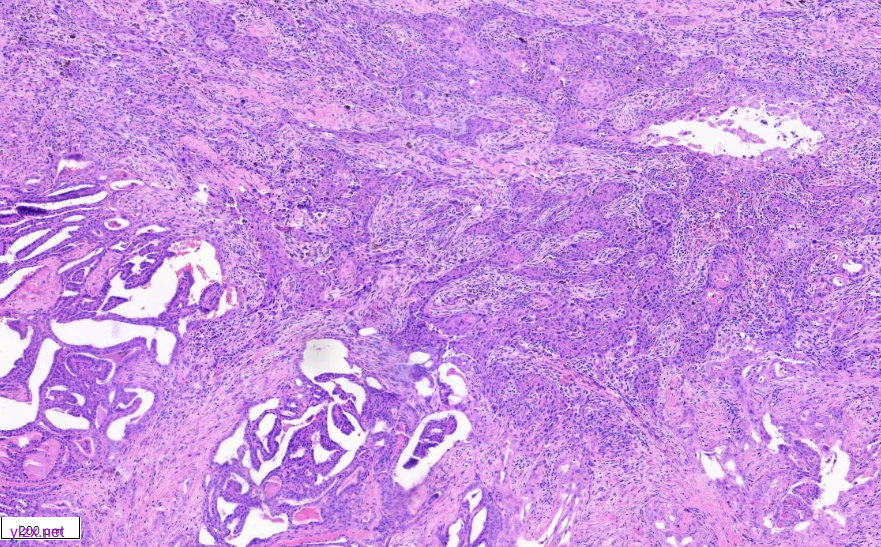

低倍镜下甲状腺乳头状癌区域与间变性癌鳞状细胞样亚型区域分界清,(图1)。低倍镜下,可见甲状腺乳头状癌呈乳头状、片状、索状分布,间质硬化(图2)。20倍镜,肿瘤细胞排列呈“铁轨”样,细胞立方形,细胞质丰富,淡嗜酸,细胞核圆,大小一致,染色质粗,核位于基底,可见小核仁,核内假包含体(图3)。鳞癌样区域(HEx10)肿瘤细胞呈多边形,梭形、上皮样,胞浆嗜酸,可见不全角化,肿瘤细胞间见脂褐素,肿瘤细胞侵袭性强,浸润至周围脂肪组织(图4、图5)。

图1 低倍镜下,显示鳞癌区域核乳头状癌区域。

图2 显示经典型乳头状癌区域。